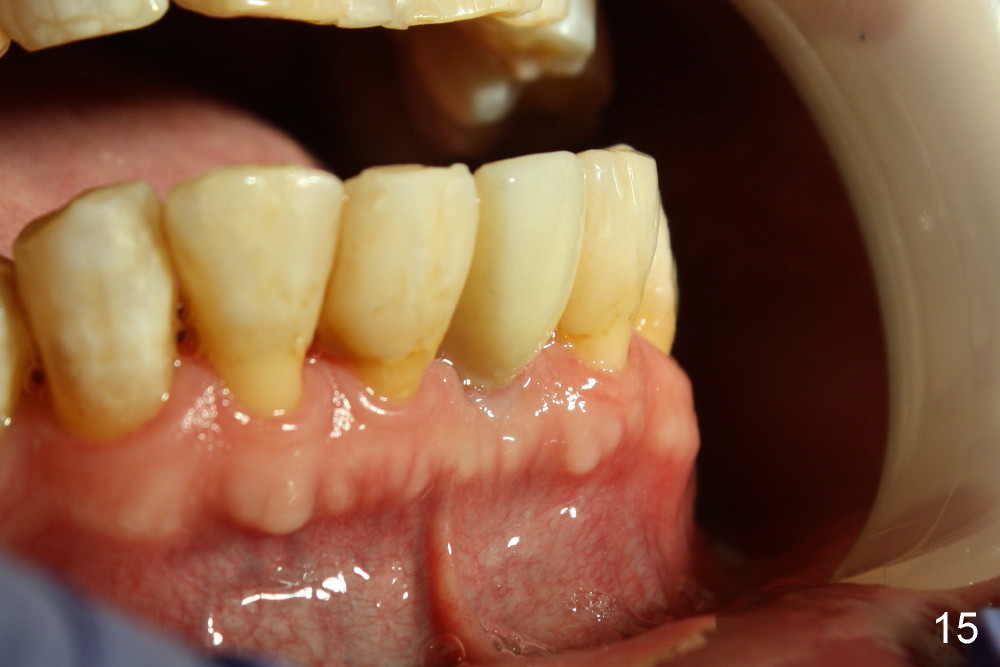

Fig.10,11 show 7 day follow up. The permanent crown is seated 4.5 months postop (Fig.12). Minimal bone resorption occurs at the crest 4 months postop (Fig.13), which is most likely associated with conservative approach (flapless). The patient returns for follow up 2.5 months post cementation (Fig.14,15). The implant remains in the bone 4 years post cementation (Fig.16 CT coronal section; lingual thread exposure, corresponding to preop defect in Fig.1). There is mild coronal bone resorption 5 years 4 months post cementation (Fig.17).